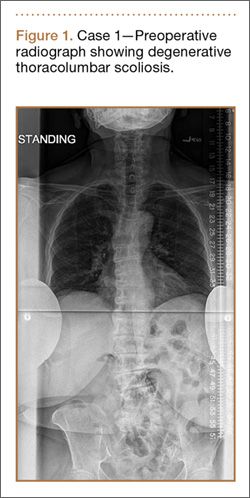

Clinical Presentation. A 78-year-old woman presented to the outpatient clinic with disability due to severe lower back pain. Her surgical history was significant for breast lumpectomy and cataract excision. Her medical history was significant for hypertension, obesity (body mass index, 31.5), hypercholesterolemia, emphysema, and anemia. She had undergone spinal surgery, specifically laminectomies from L2 to S1. The radiographic examination showed degenerative thoracolumbar scoliosis with severe spondylosis, disc space collapse, and ankylosis of L4-L5 (Figure 1).